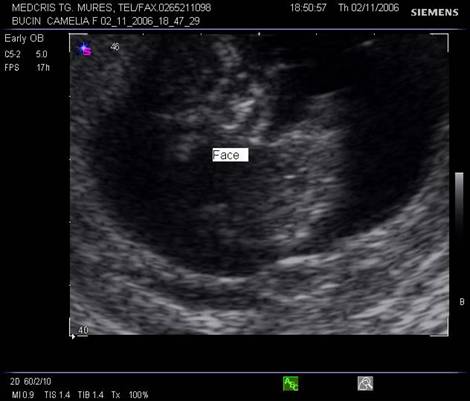

Fig. nr.23. Fata fetala la 11 sapt.